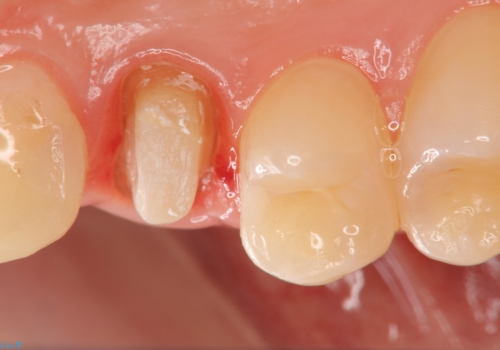

- 食事中に急に歯が折れ、周囲の歯も痛みだし治療を希望され来院されました。

ジルコニアクラウンによる咬合機能回復、根管治療を行い歯の痛みをとり長期的な予後の見込める治療を計画します。

- 26万円(仮歯・ファイバーコア・ジルコニアクラウン×2)費用は治療当時の料金となります